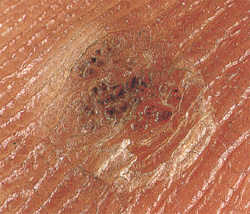

Миф номер один - бородавки появились у вас потому, что вы прикасались к лягушкам. Ничего подобного. Но бородавки могут переходить от одного человека к другому. Различают около 60 подвидов вируса папилломы человека. Данный вирус приводит к образованию бородавок на коже. Каждый из нас ежедневно подвергается воздействию этого вируса, прикасаясь к людям с бородавками или предметам, которые они трогали. Однако до последнего времени никто не может точно объяснить, почему у одних людей появляются бородавки, а у других нет. Бородавки столь же разнообразны, как и вызывающие их вирусы. И все же выделяются несколько основных видов бородавок.

Обычные бородавки. Их часто можно видеть у детей. Это выпуклые грубые образования. Плоские бородавки, как правило, имеют гладкую поверхность, по цвету приближаются к коже и слегка возвышаются над нею. Такие бородавки часто встречаются на коже рук, лица или нижней части ног у женщин, которые сбривают волосы на ногах. Подошвенные бородавки обнаруживаются на нижней поверхности стопы и ладонные бородавки - на ладонях рук. Нитевидные бородавки напоминают пучки щетины, выступающей над поверхностью кожи.

Бородавки половых органов называются кондиломами. Если их оставить без лечения, возможно возникновение более серьезных расстройств.